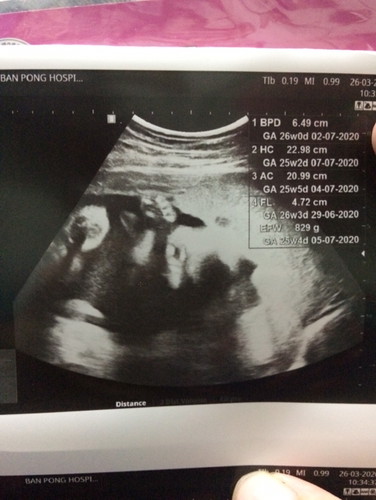

ภาพอุลตร้าซาวด์ใบนี้ บอกเพศได้ไหมคะ. เพศหญิงเพศชาย. ดูตรงไหน

ในรูปเหมือนไม่ใช้ ช่วงระหว่างขาค่ะ ภาพไม่ค่อยชัดด้วย ที่เห็นน่าจะเป็นแขนและมือน้องนะค่ะ อีอันเหมือนเท้าน้องเลย รึป่าว ดูไม่ค่อยชัด ครั้งน่าถามหมอนะค่ะ ว่า ได้ ญ หรือ ช ค่ะ

อันนี้มือค่ะ กำมืออยู่ มีครบ 5 นิ้วเลย

ดูออกแต่มือน้องค่ะแม่